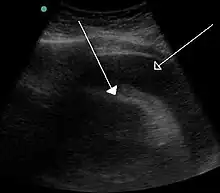

A large anechoic (black) pericardial effusion as seen on ultrasound. Closed arrow: the heart, open arrow: the effusion

Echocardiogram (ultrasound): when pericardial effusion is suspected, echocardiography usually confirms the diagnosis and allows assessment of the size, location and signs of hemodynamic instability.[4] A transthoracic echocardiogram (TTE) is usually sufficient to evaluate pericardial effusion and it may also help distinguish pericardial effusion from pleural effusion and MI. Most pericardial effusions appear as an anechoic area (black or without an echo) between the visceral and the parietal membrane.[1] Complex or malignant effusions are more heterogeneous in appearance, meaning they may have variations in echo on ultrasound.[5] TTE can also differentiate pericardial effusion based on the size. Although it's difficult to define size classifications because they vary with institutions, most commonly they are as follows: small <10, moderate 10–20, large >20.[5] An echocardiogram is urgently needed for evaluation when there is concern for hemodynamic compromise, a rapidly developing effusion or history of recent cardiac surgery/procedures.[1]